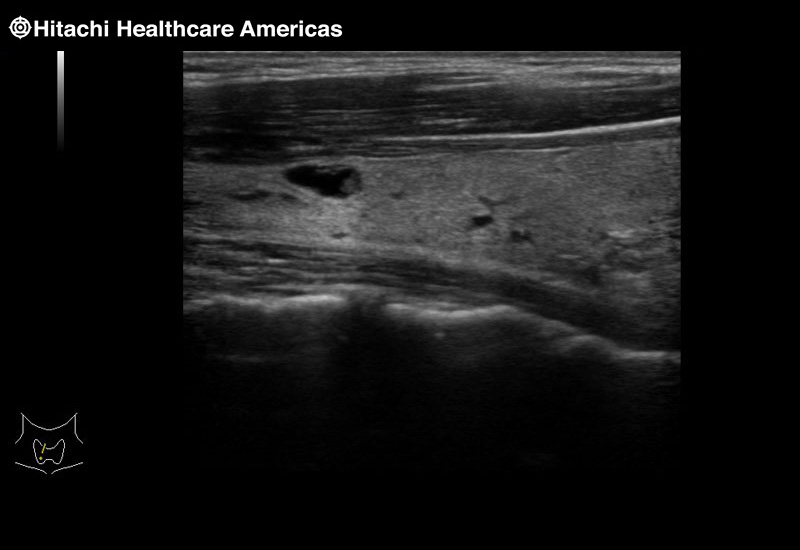

Superior guidance for all applications

Fujifilm Healthcare Americas is committed to designing tools that help surgeons navigate inside the human body and provide the necessary information to immediately make critical surgical decisions.

Fujifilm Healthcare's dedication to Surgeons provides outstanding ultrasound technology, professional support and the specialized tools necessary to best perform comprehensive real-time ultrasound imaging in Breast Surgery, General Surgery, Laparoscopic Surgery, Neurosurgery, Robotic Surgery and Surgical Oncology.